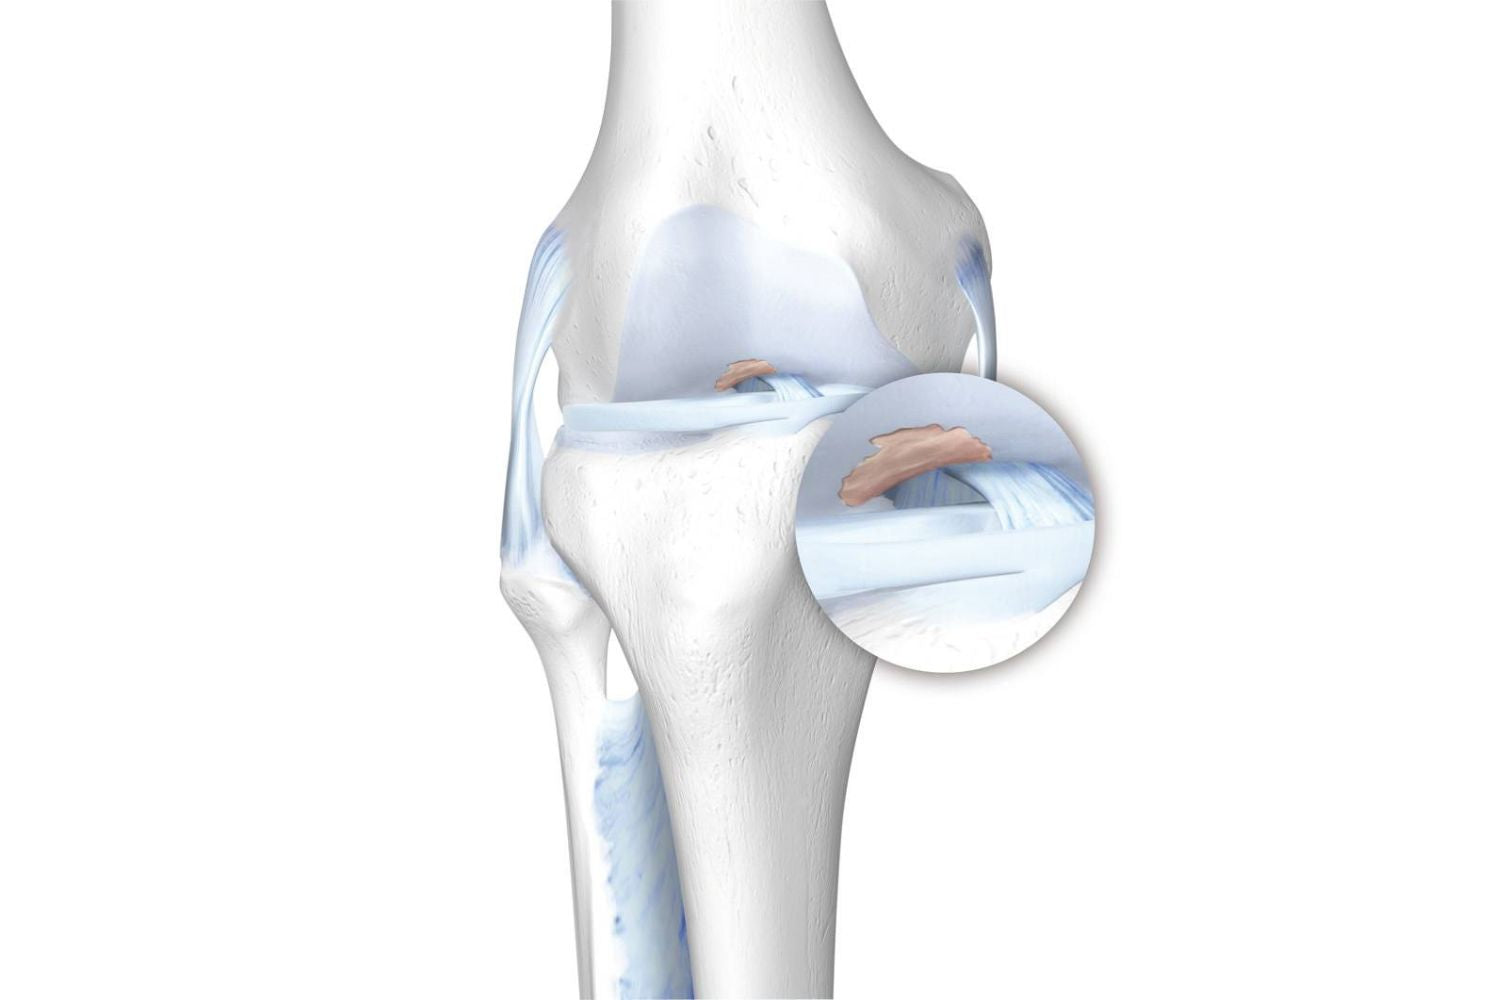

A defect in the knee joint cartilage can be the beginning of arthritis in the knee. The cartilage wears gradually, placing more pressure on the bones that form the knee joint.

The inflammation caused by this wear and tear triggers a response in the bone to grow additional spurs of bone (osteophytes) at the edges of the knee joint. As the damage to the cartilage increases, the knee joint becomes less mobile, and the joint space becomes smaller.